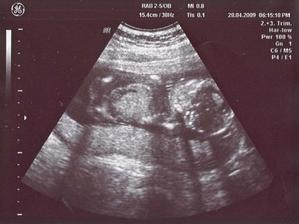

28/4 09 PORADNA 19 + 2 tt - mimís byl krásně otočenej k nám, šlo vidět pěkně mezi nožky ... je to holka ... na 99% - dr. si asi nechává rezervu ... máme další fotečku, krevní testy taky dopadly ok, 7.5. jdu ještě na genet. utz